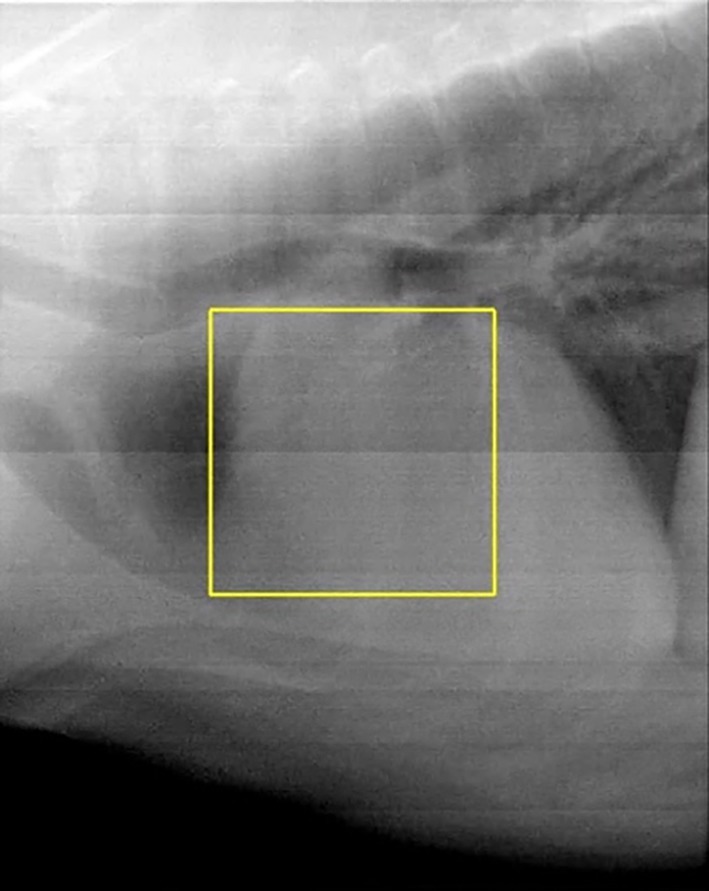

Canine cardiac hemangiosarcoma (cHSA) represents a complex clinical challenge in that those afflicted have an acute risk of death due to cardiac tamponade and high morbidity and mortality given the frequency of metastasis. Previous studies show that radiation therapy (RT) can decrease the risk of tamponade; however, an optimal approach has yet to be determined. The objective of this study was to evaluate the outcomes of dogs with presumptive cHSA treated with varied RT protocols and modalities, and to contrast findings with previously published literature. Secondary objectives were to assess differences in outcomes between those that received chemotherapy post-RT or did not, single fraction versus multiple-fraction RT protocols, and CT-guided versus manually calculated treatment plans. Twenty-seven dogs with echocardiographic evidence of an atrial or auricular cardiac mass that received RT were included. The frequency of pericardiocentesis before and post-RT were compared. Overall survival time was determined, along with survival time specific to those that received chemotherapy, were treated with CT-based radiation plans, and were prescribed a single fraction versus multiple fractions. Pericardiocentesis was performed an average of 1.1 times per week before RT, and an average of 0.18 times per week after RT (p = 0.01). Median overall survival time was 137 days. Plans made without CT guidance were associated with more adverse radiation events, but all were minimally impactful on quality of life. Most dogs died or were euthanized due to metastatic disease. This study shows similar benefits to previously published data in a larger cohort of dogs using a less-conformal radiation modality. As well, it highlights future directions to identify optimal systemic therapies to delay the onset of metastasis.